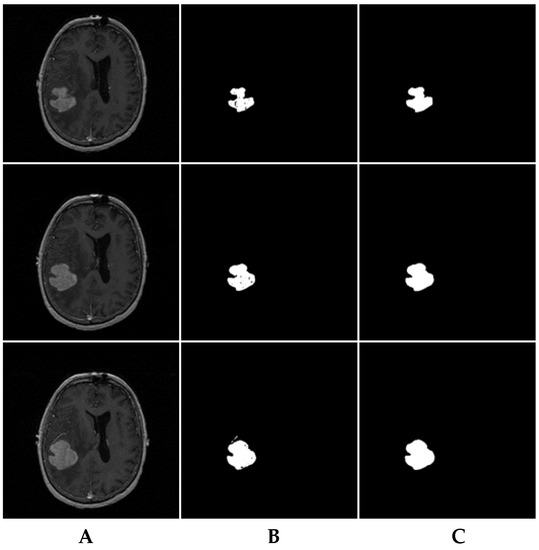

Under this segmentation process, some brain tumor parts in the MRI slices were incorrectly segmented as healthy tissues, and some healthy brain tissues were incorrectly segmented as pathological tissues. To eliminate these ambiguities and reduce the FPs and FNs, a consistency verification algorithm was applied for post-processing [11,40]. The majority filter was adopted to remove the FPs and FNs by replacing the segmented pixels inconsistent with their neighboring segmented pixels in a certain neighborhood. For example, if the center pixel of a window is segmented as a tumor but the majority of the neighboring pixels were segmented as healthy, then the center pixel is changed to healthy. Otherwise, if a pixel within the tumor area is segmented incorrectly as healthy and is surrounded by pixels that are segmented as tumor, then the pixel is changed to a pathological pixel. If the window size of the applied filter is increased, the quality of the output image significantly augments at the expense of complexity increase [40]. Herein, consistency verification was applied in a 5 × 5 neighborhood window [11].

For instance, the MRI brain slices in Figure 11A include some MRI slices with incorrectly segmented pixels (Figure 11B). The consistency verification algorithm results are shown in Figure 11C. Table 2 and Table 3 demonstrate the average results of segmentation for both collected and BRATS 2013 datasets, respectively, in which the collected dataset was manually segmented by experts.

Figure 11. Results after applying the consistency verification algorithm. (A) original MRI slices; (B) segmented MRI brain slices by 3DACWE; (C) output of consistency verification algorithm.